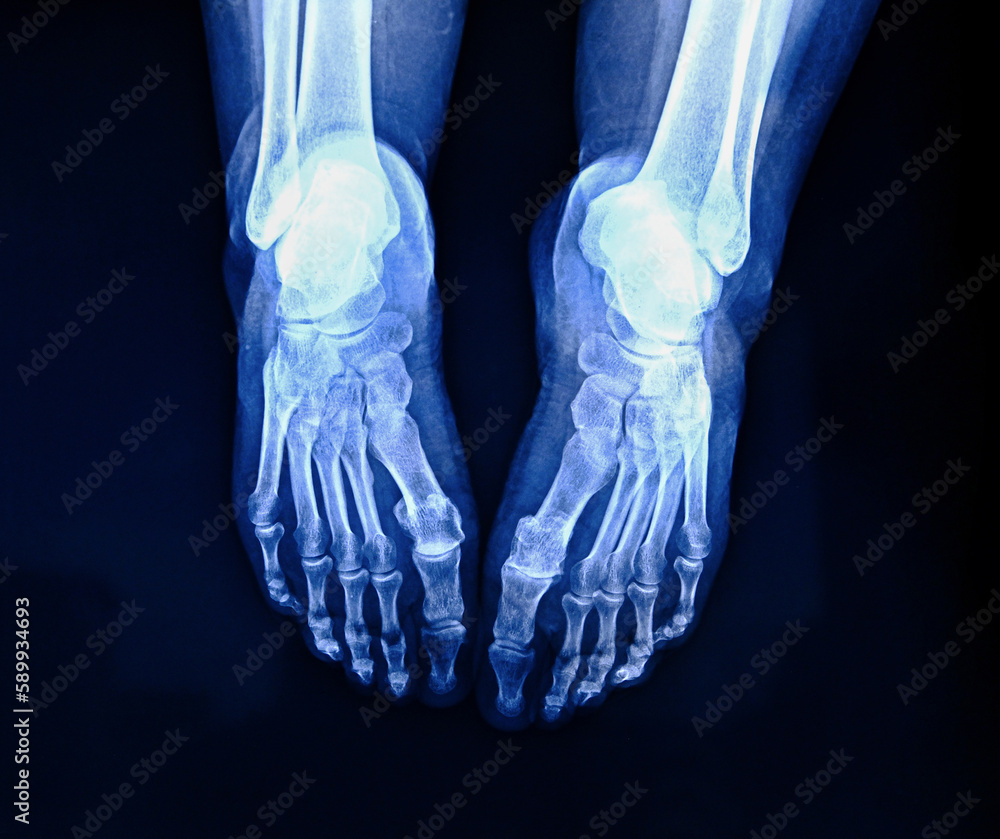

Xray shows injuries from crash where passenger had feet on dash

Xray Of Feet On Dashboard . The injuries in a crash could be severe, and even a minor. Doctors said a young woman in the passenger seat of a vehicle had her feet up on the dashboard before a crash. Police have shared a shocking image of a car crash victim’s injuries in an effort to stop passengers putting their feet on a car’s. Not only did the impact shunt her legs backward, the airbag deploying caused her pelvis to become dislocated and her knees to then impact her face breaking her jaw bone. You surely know that riding with feet up on the dashboard is unsafe.

You surely know that riding with feet up on the dashboard is unsafe. Police have shared a shocking image of a car crash victim’s injuries in an effort to stop passengers putting their feet on a car’s. The injuries in a crash could be severe, and even a minor. Not only did the impact shunt her legs backward, the airbag deploying caused her pelvis to become dislocated and her knees to then impact her face breaking her jaw bone. Doctors said a young woman in the passenger seat of a vehicle had her feet up on the dashboard before a crash.